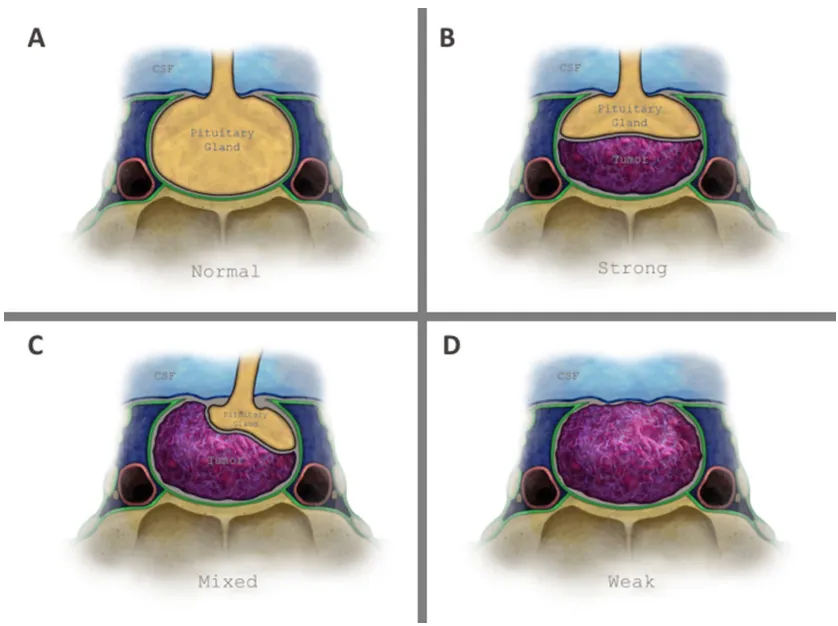

垂体肿瘤与鞍上脑脊液之间的界面由三层结构构成:蛛网膜组织(唯一恒定结构)、鞍隔硬脑膜及垂体腺(图1a)。基于此解剖基础,福教授前期研究通过脑磁共振成像定义了两种鞍隔屏障亚型:薄弱型与强韧型,后续研究进一步提出了混合型屏障的概念(图1b-d)。

图1垂体窝顶壁解剖结构及鞍隔屏障分型示意图。

a无肿瘤状态下的正常解剖结构;b强韧型鞍隔屏障:垂体腺和/或硬脑膜位于肿瘤与脑脊液之间。图示案例为单纯由垂体腺构成的强韧型屏障;c混合型鞍隔屏障:肿瘤部分区域直接接触蛛网膜下腔,部分区域接触垂体腺;d薄弱型鞍隔屏障:肿瘤与鞍隔顶壁全界面直接接触蛛网膜下腔。